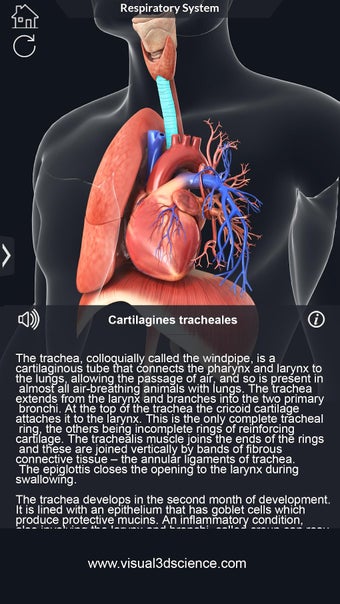

呼吸器系の解剖学は、肺、気管、およびすべての気道を含む呼吸器系の解剖学の研究です。最も一般的なアプローチは、系を上部と下部に分割することです。上部には気管、主気管支、および終末および前頸気道が含まれます。下部には肺と最小の大きさの末梢気道が含まれます。これらの部分それぞれには特徴的な外観と機能があります。

このアプリケーションは、高度にリアルな呼吸器系のモデルです。ユーザーは任意の角度および任意の平面から呼吸器系の解剖学を表示できます。ユーザーは360°回転し、ズームインおよびズームアウトして解剖学をよりよく研究することができます。ユーザーはまた、画面に描画するためのさまざまなツールを使用して写真を撮ることもできます。